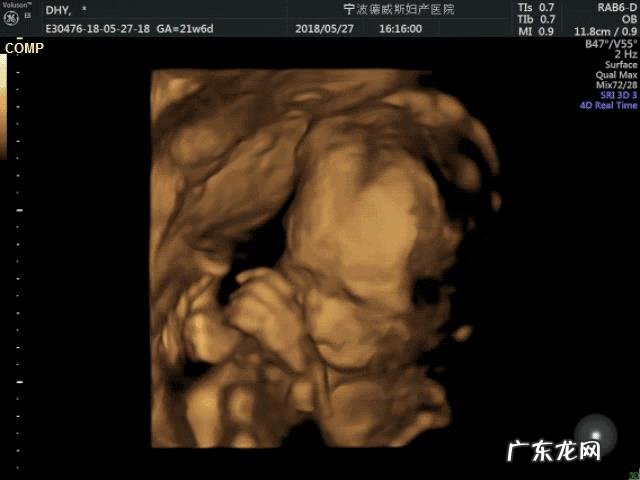

四维彩超属于一种排畸检查,可以看到宝宝的身体结构方面比较大的畸形,但对于比较小的畸形,四维彩超是不能100%看出来的,就连心脏畸形也是一样的,只能排除30%-50%的心脏问题,所以有的地方的医院的产检项目包括胎儿心脏彩超检查,为的就是这个原因 。

四维可以检查出胎儿的性别,四维彩超也叫大排畸,很大部分可以检查胎儿面部畸形,对于胎儿的神经系统,也可以检查出是否有无脑儿和脑积水的情况,还可以胎儿的肾积水,如果孕妈的羊水浑浊和羊水量的多少也是可以检查的,但是一些比较隐蔽的是很难检查出来的,比如胎儿的智力和视力是无法检查出来的,还有一些先天性心脏病和手指脚趾的畸形都是很难检查出来 。